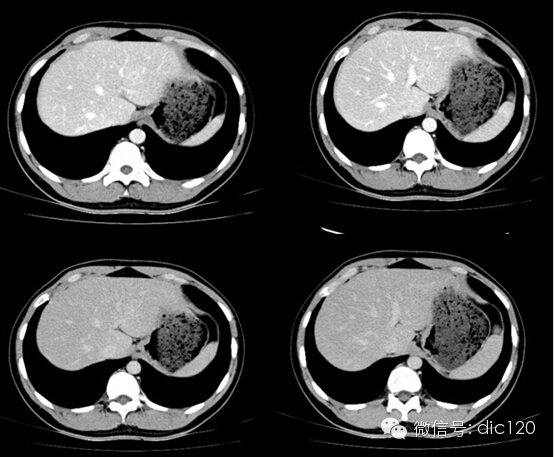

影像表現:CT平掃與正常肝組織呈等密度,密度均勻,動脈期病灶快速明顯均勻強化,中心見小片狀低密度影(瘢痕),門脈期及延遲期對比劑快速退出呈等密度,中央低密度影延遲強化。MRI腫塊T2WI為稍高信號,中央高信號。動態增強掃描動脈期均顯著增強,門脈期輕度增強,延遲期瘢痕強化。

FNH具有離心性血液供應及二條血液引流途徑。FNH的典型CT表現包括增強早期腫瘤呈彌漫均勻強化,在門靜脈期或門靜脈后期成等密度,病灶內可見中心低密度瘢痕及輻射狀分隔,腫瘤周圍有薄而不完整的包膜樣血管。瘢痕是FNH 另一個重要影像學表現,尤其是延遲掃描瘢痕強化為其特征。